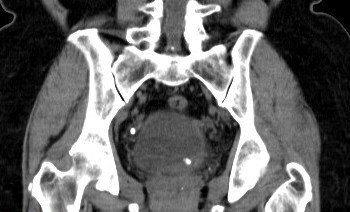

Abdominal CT images